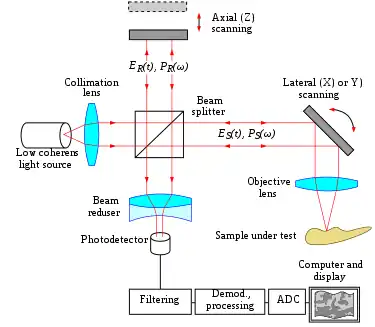

Figure 22. Typical optical setup of single point OCT |

Optical coherence tomography (OCT) is a medical imaging technique using low-coherence interferometry to provide tomographic visualization of internal tissue microstructures. As seen in Fig. 22, the core of a typical OCT system is a Michelson interferometer. One interferometer arm is focused onto the tissue sample and scans the sample in an X-Y longitudinal raster pattern. The other interferometer arm is bounced off a reference mirror. Reflected light from the tissue sample is combined with reflected light from the reference. Because of the low coherence of the light source, interferometric signal is observed only over a limited depth of sample. X-Y scanning therefore records one thin optical slice of the sample at a time. By performing multiple scans, moving the reference mirror between each scan, an entire three-dimensional image of the tissue can be reconstructed.[101][102] Recent advances have striven to combine the nanometer phase retrieval of coherent interferometry with the ranging capability of low-coherence interferometry.[74]